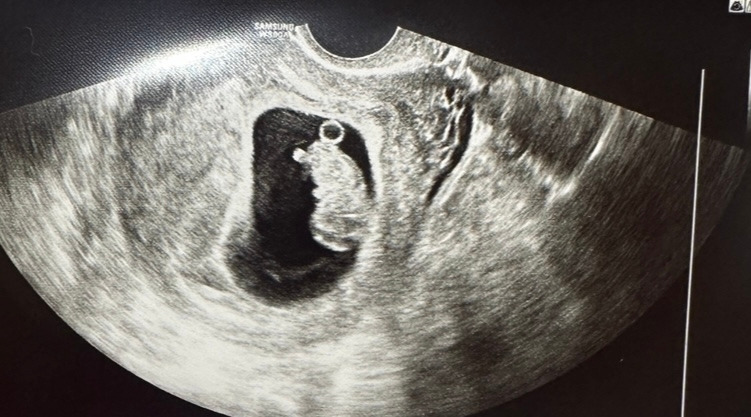

귀여운 나의 아기 하리보

12주 차

매주 건강하게 잘 자라고 있는 우리 아기곰